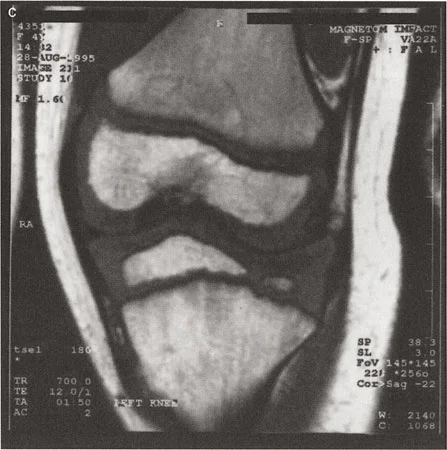

في الركبة الطبيعية والصحية، يكون خط المفصل لعظم الفخذ البعيد (المرسوم عبر أبعد النقاط الإنسية والوحشية للقمم الفخذية) وخط المفصل لعظم الساق القريب (المرسوم عبر الهضبتين الظنبوبيتين الإنسية والوحشية) متوازيين تقريباً. ينتج عن هذه العلاقة المتوازية فراغ مفصلي متطابق تماماً يوزع الحمل بالتساوي عبر الغضروف المفصلي أثناء دورة المشي. تتراوح الزاوية التوافقية لخط المفصل الطبيعية عادةً بين 0 و 2 درجة.

عندما يفقد الغضروف بشكل غير متماثل - كما هو الحال في التهاب المفاصل الكلاسيكي في الجزء الإنسي من الركبة - أو عندما تنخفض الهضبة الظنبوبية جسدياً بسبب صدمة عالية الطاقة أو مرض نمائي، تفقد هذه الخطوط المفصلية علاقتها المتوازية. التأثير البيوميكانيكي هو زيادة مرضية في الزاوية التوافقية لخط المفصل. كلما زادت هذه الزاوية، تتضاعف قوى القص عبر المفصل، مما يسرع المزيد من تدهور الغضروف ويزيد من انحراف المحور الميكانيكي.

خلل التنسج وسوء التوجيه عندما لا يكفي خط واحد

حتى هذه النقطة في التخطيط القياسي للتشوهات، نفترض أن خطاً مستقيماً واحداً يمكن أن يمثل بدقة خط مفصل الساق القريب، وخطاً آخر يمكن أن يمثل عظم الفخذ البعيد. يربط هذا الخط أبعد النقاط الإنسية والوحشية للقمم الفخذية، أو أعلى النقاط الإنسية والوحشية للهضبتين الظنبوبيتين. ونظراً لأن هذه النقاط عادة ما تكون متوازية ومتماثلة نسبياً، فإن خطاً واحداً يكفي.

ومع ذلك، فإن خلل تنسج لقمة أو هضبة واحدة بالنسبة للأخرى - سواء كان من أصل خلقي أو نمائي أو معدي أو رضحي - يدمر هذه العلاقة المتوازية. والنتيجة هي لقمة أو هضبة واحدة منحرفة أو متدرجة أو منخفضة بالنسبة لنظيرتها. يصبح الخط الواحد المرسوم عبر هذا السطح الفوضوي عديم المعنى رياضياً.